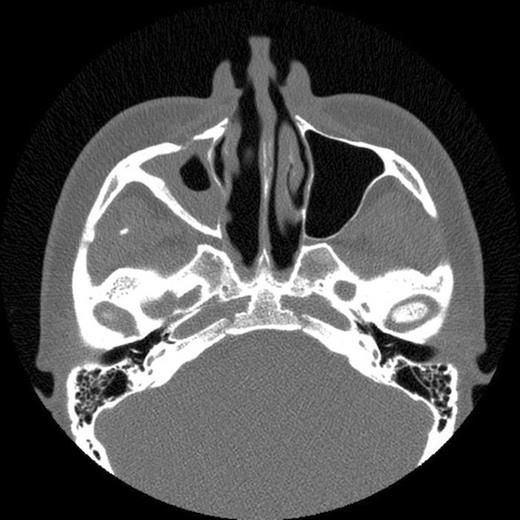

The patient then attended our clinic. Clinical examination and subsequent naso-endoscopy showed evidence of a right sided nasal obstruction with polypoidal mass within the nasal cavity. The patient underwent CT scan sinuses, which showed a well demarcated air defect in the extensively thickened sinus mucosa with large polypoidal mass. Evidence of entry of the cue was seen as a defect in the anterolateral wall of the right maxillary sinus and absent upper medial wall. No FB was seen.

CT scan showing fracture of the anterolateral wall of the right maxillary sinus and absent upper medial wall

The history and CT scan results suggest that following penetration of the snooker cue into the gingivo-labial sulcus it had broken through the right anterolateral maxillary wall and upper medial wall. On withdrawal of the snooker cue, the cue tip had broken off in the maxillary sinus. The FB had then caused localised inflammation resulting in episodes of sinusitis and facial pain. The FB had subsequently been discharged during a coughing episode 12 years later.